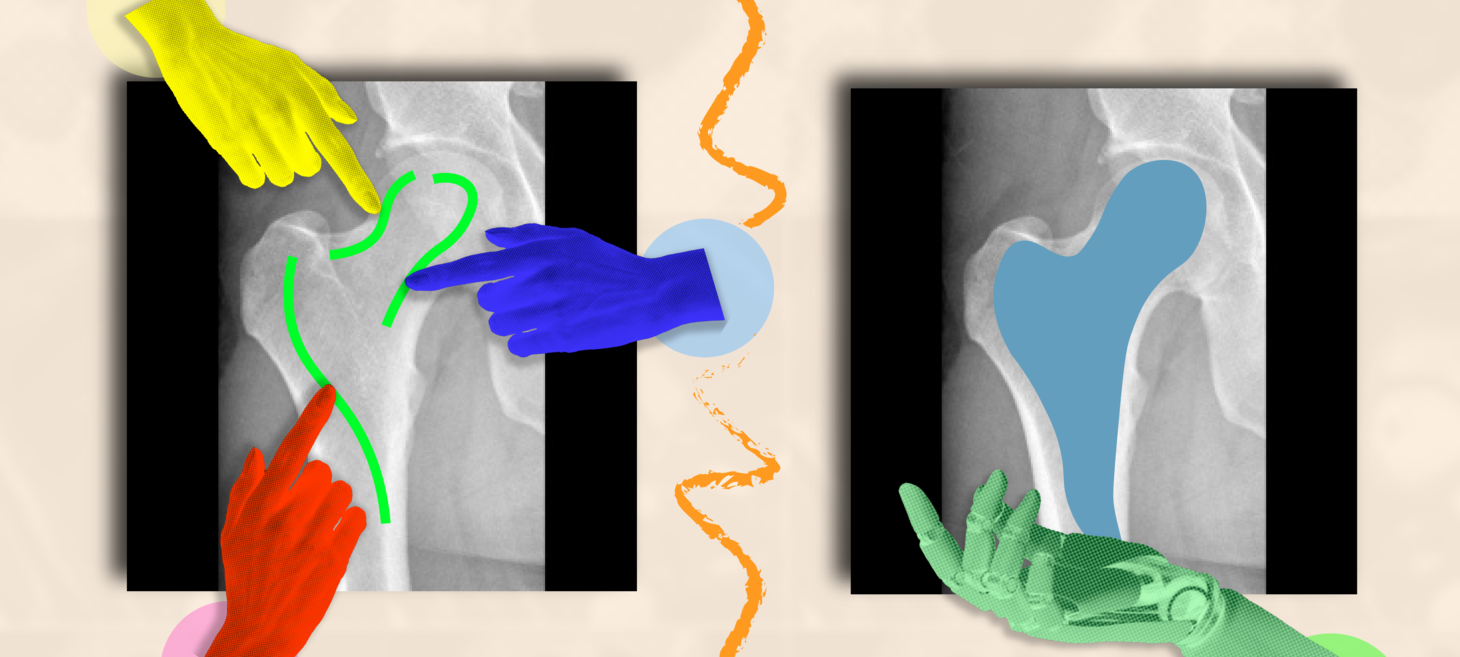

A fast and flexible approach to help doctors annotate medical scans

“ScribblePrompt” is an interactive AI framework that can efficiently highlight anatomical structures across different medical scans, assisting medical workers to delineate regions of interest and abnormalities.

news.mit.edu